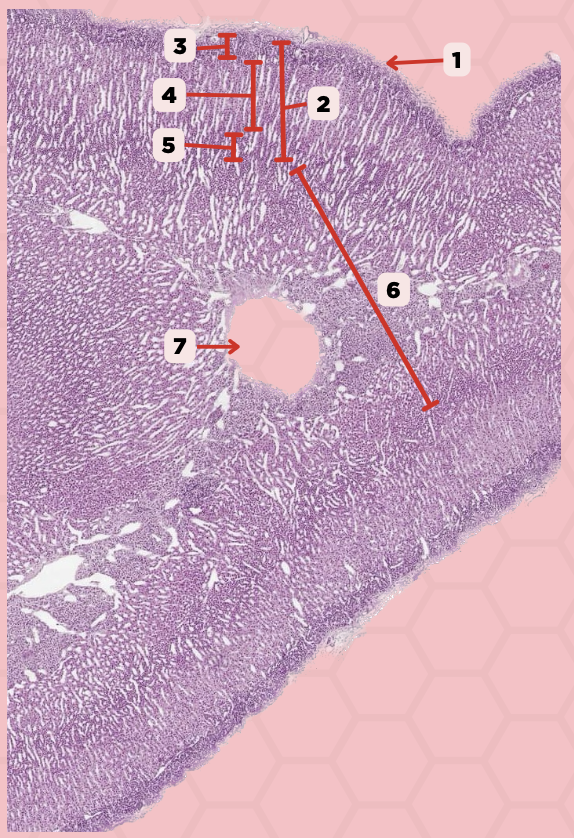

Adrenal

Identify the specimen.

Connective Tissue Capsule

Identify the structure labeled as 1.

Cortex

Identify the structure labeled as 2.

Medulla

Identify the structure labeled as 3.

Medullary Veins

Identify the structure labeled as 4.

Zone Glomerulosa

This layer seen in pointer #3 consists of rounded or pyramidal epithelial cells that arranges in irregular ovoid clusters that are separated by sinusoids

Mineralocorticoids, Glucocorticoids, Androgens

What are the 3 classes of Adrenocortical Hormones?

Zone Glomerulosa

Identify the structure labeled as 1.

Zona Fasciculata

Identify the structure labeled as 2.

Zona Reticularis

Identify the structure labeled as 3.

Androgens

What hormones are produced from the layer seen in pointer #5?